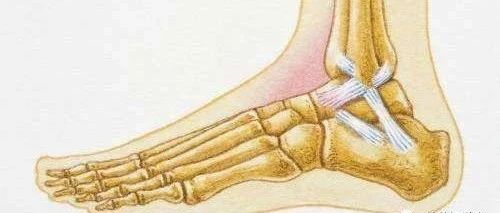

来源:足踝外科电子杂志作者:大连医科大学附属第二医院手足外科  刘学晖创伤性关节炎(PTA)以与关节损伤有关的关节软骨退化改变为特点。踝关节对关节损伤尤其敏感,更易导致PTA的发生。据报道,创伤性踝关节炎占继发性踝关节炎的65%~80%。终末期的踝关节炎常表现为持续的负重疼痛甚至自发性疼痛,功能受限或丧失,伴或不伴畸形,对患者的生活及工作影响巨大,在生命质量测评上,终末期踝关节炎毁灭性的后遗症堪比髋关节炎、充血性心力衰竭和终末期肾病。传统的治疗终末期踝关节炎的可靠方法是踝关节固定术,如胫距关节融合术、全踝关节融合术等,但会对邻近关节造成负面影响,导致邻近关节的关节炎,在融合术后畸形愈合的病例中更为明显。为保留关节活动度和避免邻近关节关节炎的发生,医者们开始应用全踝关节成形术(TAA)拯救终末期踝关节炎。然而,两种方法远期效果都不能令人满意。...

踝关节牵张治疗创伤性踝关节炎的研究进展